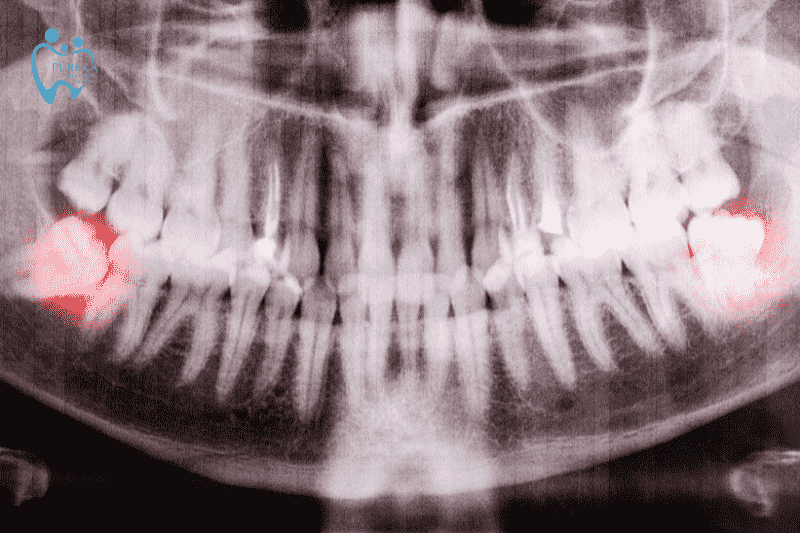

Việc nhổ dự phòng răng khôn hàm dưới mọc lệch, mọc ngầm có thể giúp tránh được những tai biến đau nhức cho người bệnh. Khi nhổ răng khôn cần đi khám chuyên khoa. Bác sĩ sẽ dựa trên phim X-quang để xác định vị trí, chiều thế và phương pháp nhổ thích hợp.

- Vị trí: Nằm phía trong cùng của hai hàm răng, hay còn gọi là răng cối thứ ba. Chúng thường mọc sau răng số 7 và ngay góc hàm

2.2 Một số tình trạng mọc răng khôn phổ biến

- Răng khôn mọc đúng hướng (vertical impaction): Răng mọc thẳng và đúng vị trí ở trong hàm, không gây đau, sưng tấy hoặc viêm nhiễm nướu, cho thấy rằng hàm răng có đủ không gian và điều kiện để răng khôn phát triển bình thường

- Răng khôn lệch trái hoặc phải (mesial/distal impaction): Do không gian chật hẹp, hàm không đủ chỗ để chứa răng khôn mới, làm răng mọc lệch hướng và ảnh hưởng đến các răng lân cận. Thức ăn cũng dễ mắc kẹt giữa răng khôn và nướu bên trên khiến việc làm sạch trở nên vô cùng khó khăn

- Răng khôn chỉ mọc một phần (partial impaction): Vài người chỉ phát triển một phần răng khôn, tạo ra khoảng trống giữa răng khôn và các răng khác. Đây là điều kiện thuận lợi cho vi khuẩn và mảng bám hình thành, dẫn đến viêm nhiễm nướu và sưng tấy

- Răng khôn mọc ngang hoặc nghiêng (horizontal impaction): Một số trường hợp đặc biệt răng khôn có thể mọc nghiêng hoặc nằm ngang, không thể mọc thẳng đứng bình thường làm cho nướu đau, tạo áp lực và có khả năng xung huyết trong những vùng xung quanh